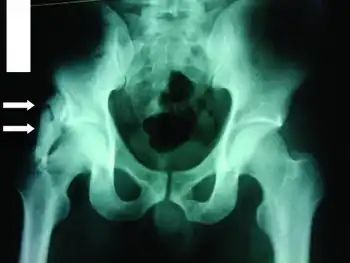

Most (i.e. 80%) ossifications arise in the thigh or arm, and are caused by a premature return to activity after an injury. Other sites include intercostal spaces, erector spinae, pectoralis muscles, glutei, and the chest. On planar x-ray, hazy densities are sometimes noted approximately one month after injury, while the denser opacities eventually seen may not be apparent until two months have passed.

The radiological features of myositis ossificans are ‘faint soft tissue calcification within 2–6 weeks, (may have well-defined bony margins by 8 weeks) separated from periosteum by lucent zone and on CT, the characteristic feature is peripheral ossification’.[10][11][12]

- Radiograph showing myositis ossificans Archived 2021-05-17 at the Wayback Machine